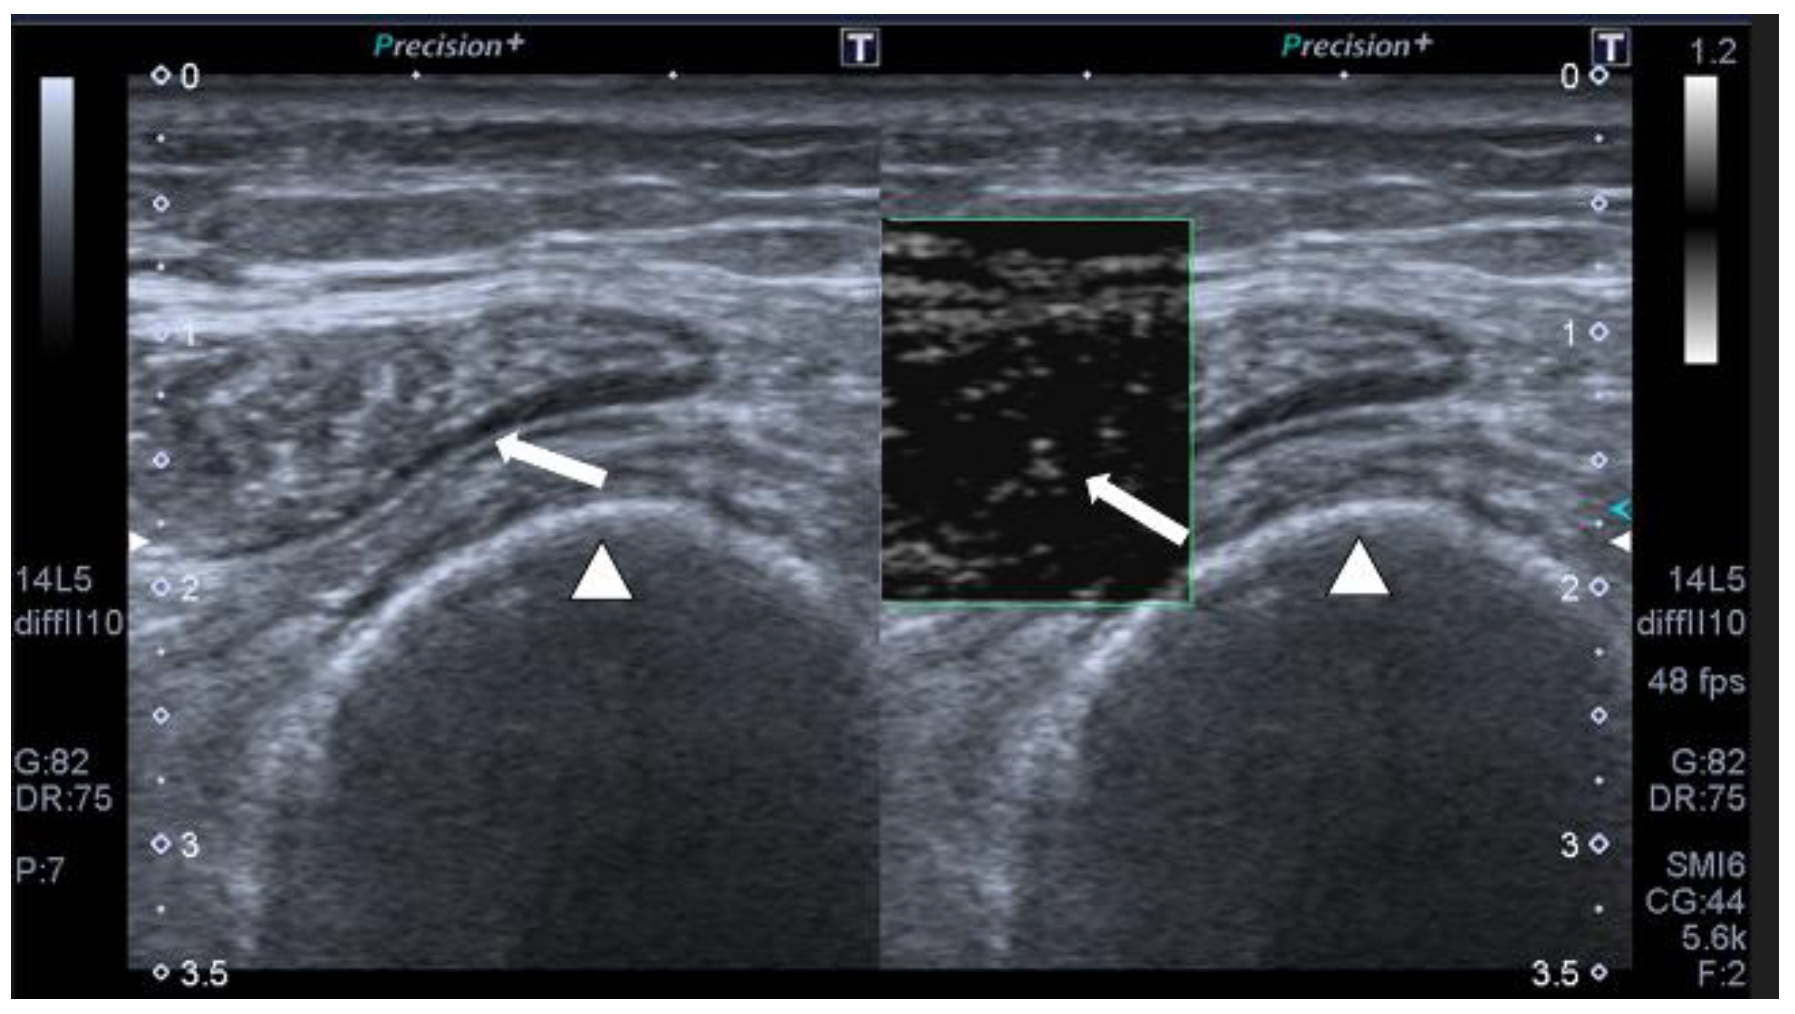

- Hernández-Socorro, C.R.; Saavedra, P.; López-Fernández, J.C.; Lübbe-Vazquez, F.; Ruiz-Santana, S. Novel high-quality sonographic methods to diagnose muscle wasting in long-stay critically ill patients: Shear wave elastography, superb microvascular imaging and contrast-enhanced ultrasound. Nutrients 2021, 13, 2224. [Google Scholar] [CrossRef]